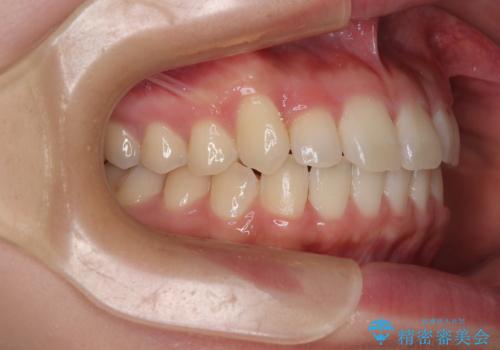

- 上下前歯のデコボコを気にして来院された患者様です。

ワイヤー矯正でもマウスピース矯正でも可能でしたが、短期間で、自身の手を煩わせることなく治療を行いたいとのことで、ワイヤー装置にて矯正治療を行うこととしました。

僅か8ヶ月という短期間で、綺麗な歯列に仕上がりました。